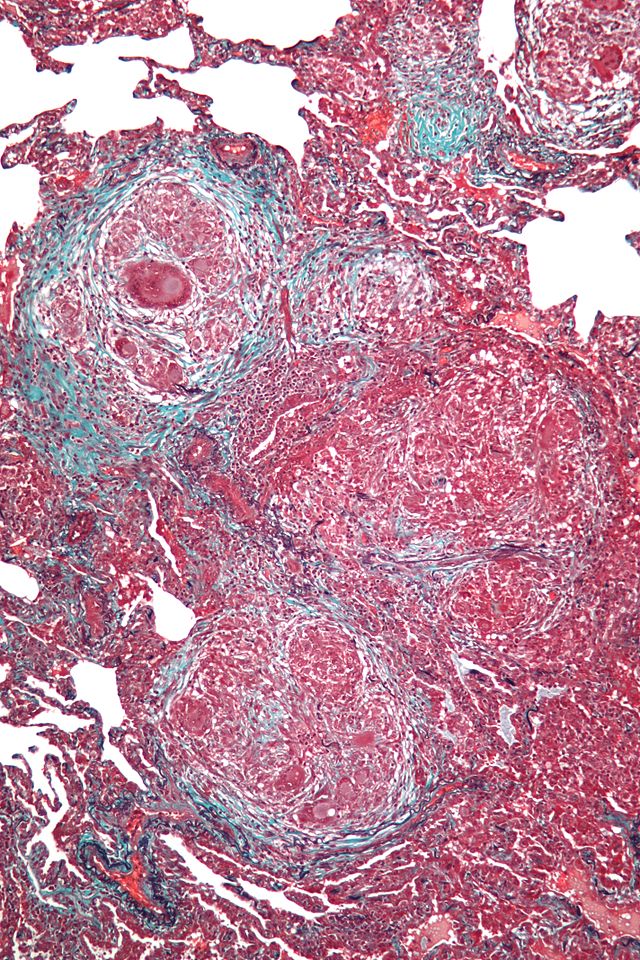

Particularités des formes fibreuses

Les PHS fibreuses sont de prise en charge plus difficile, pouvant nécessiter un prélèvement pulmonaire chirurgical. En tout état de cause le pronostic est plus sévère que la PHS inflammatoire, se rapprochant de celui de la FPI : les antifibrosants utilisés dans cette affection y ont été proposés (nintédanib, pirfénidone).